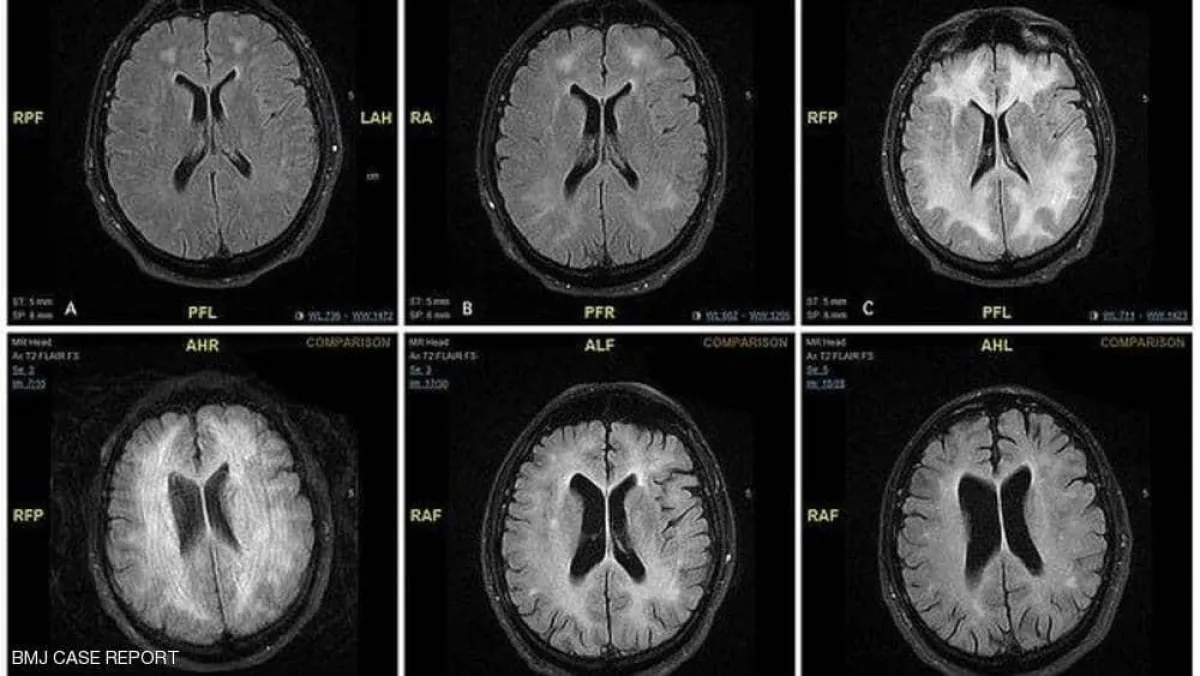

وينصح باحثون الآباء قبل تعريض أبنائهم للفحص بالأشعة المقطعية، أن يطلبوا أقل جرعة ممكنة من الإشعاع، إضافة إلى تجنب قدر الإمكان المسح المتعدد والاستفسار عن إمكانية إجراء الفحص باستخدام الموجات فوق الصوتية أو التصوير بالرنين المغناطيسي MRI عوضًا عن التصوير المقطعي.